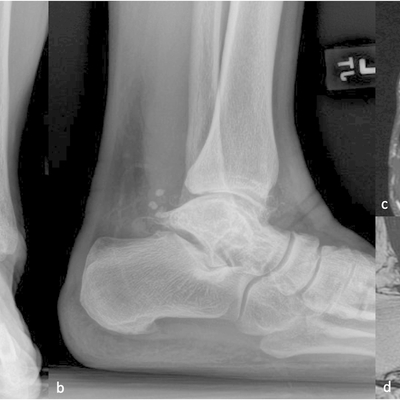

Click on an image below to view more info.